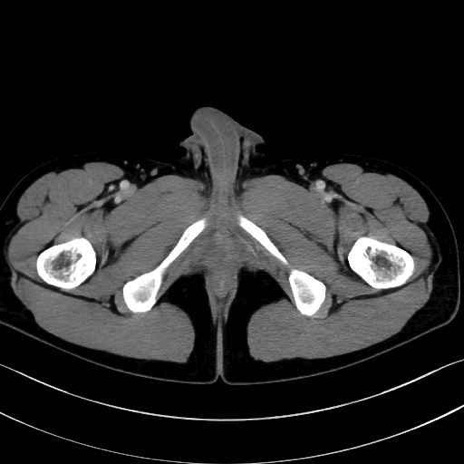

小殿筋 (Gluteus minimus)